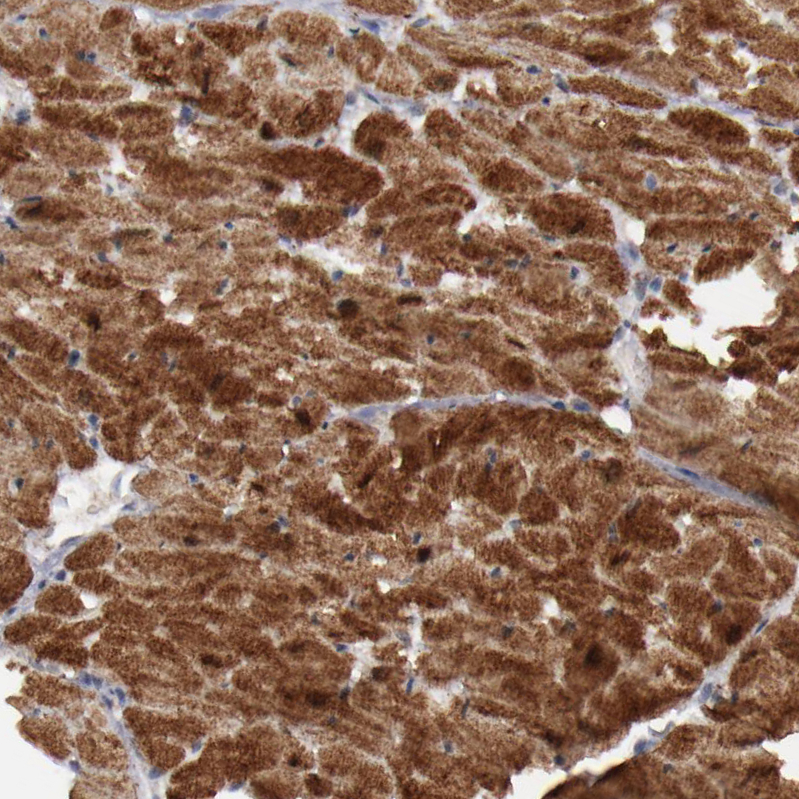

Immunohistochemistry analysis in human heart muscle and prostate tissues using HPA001765 antibody. Corresponding MYOM2 RNA-seq data are presented for the same tissues.